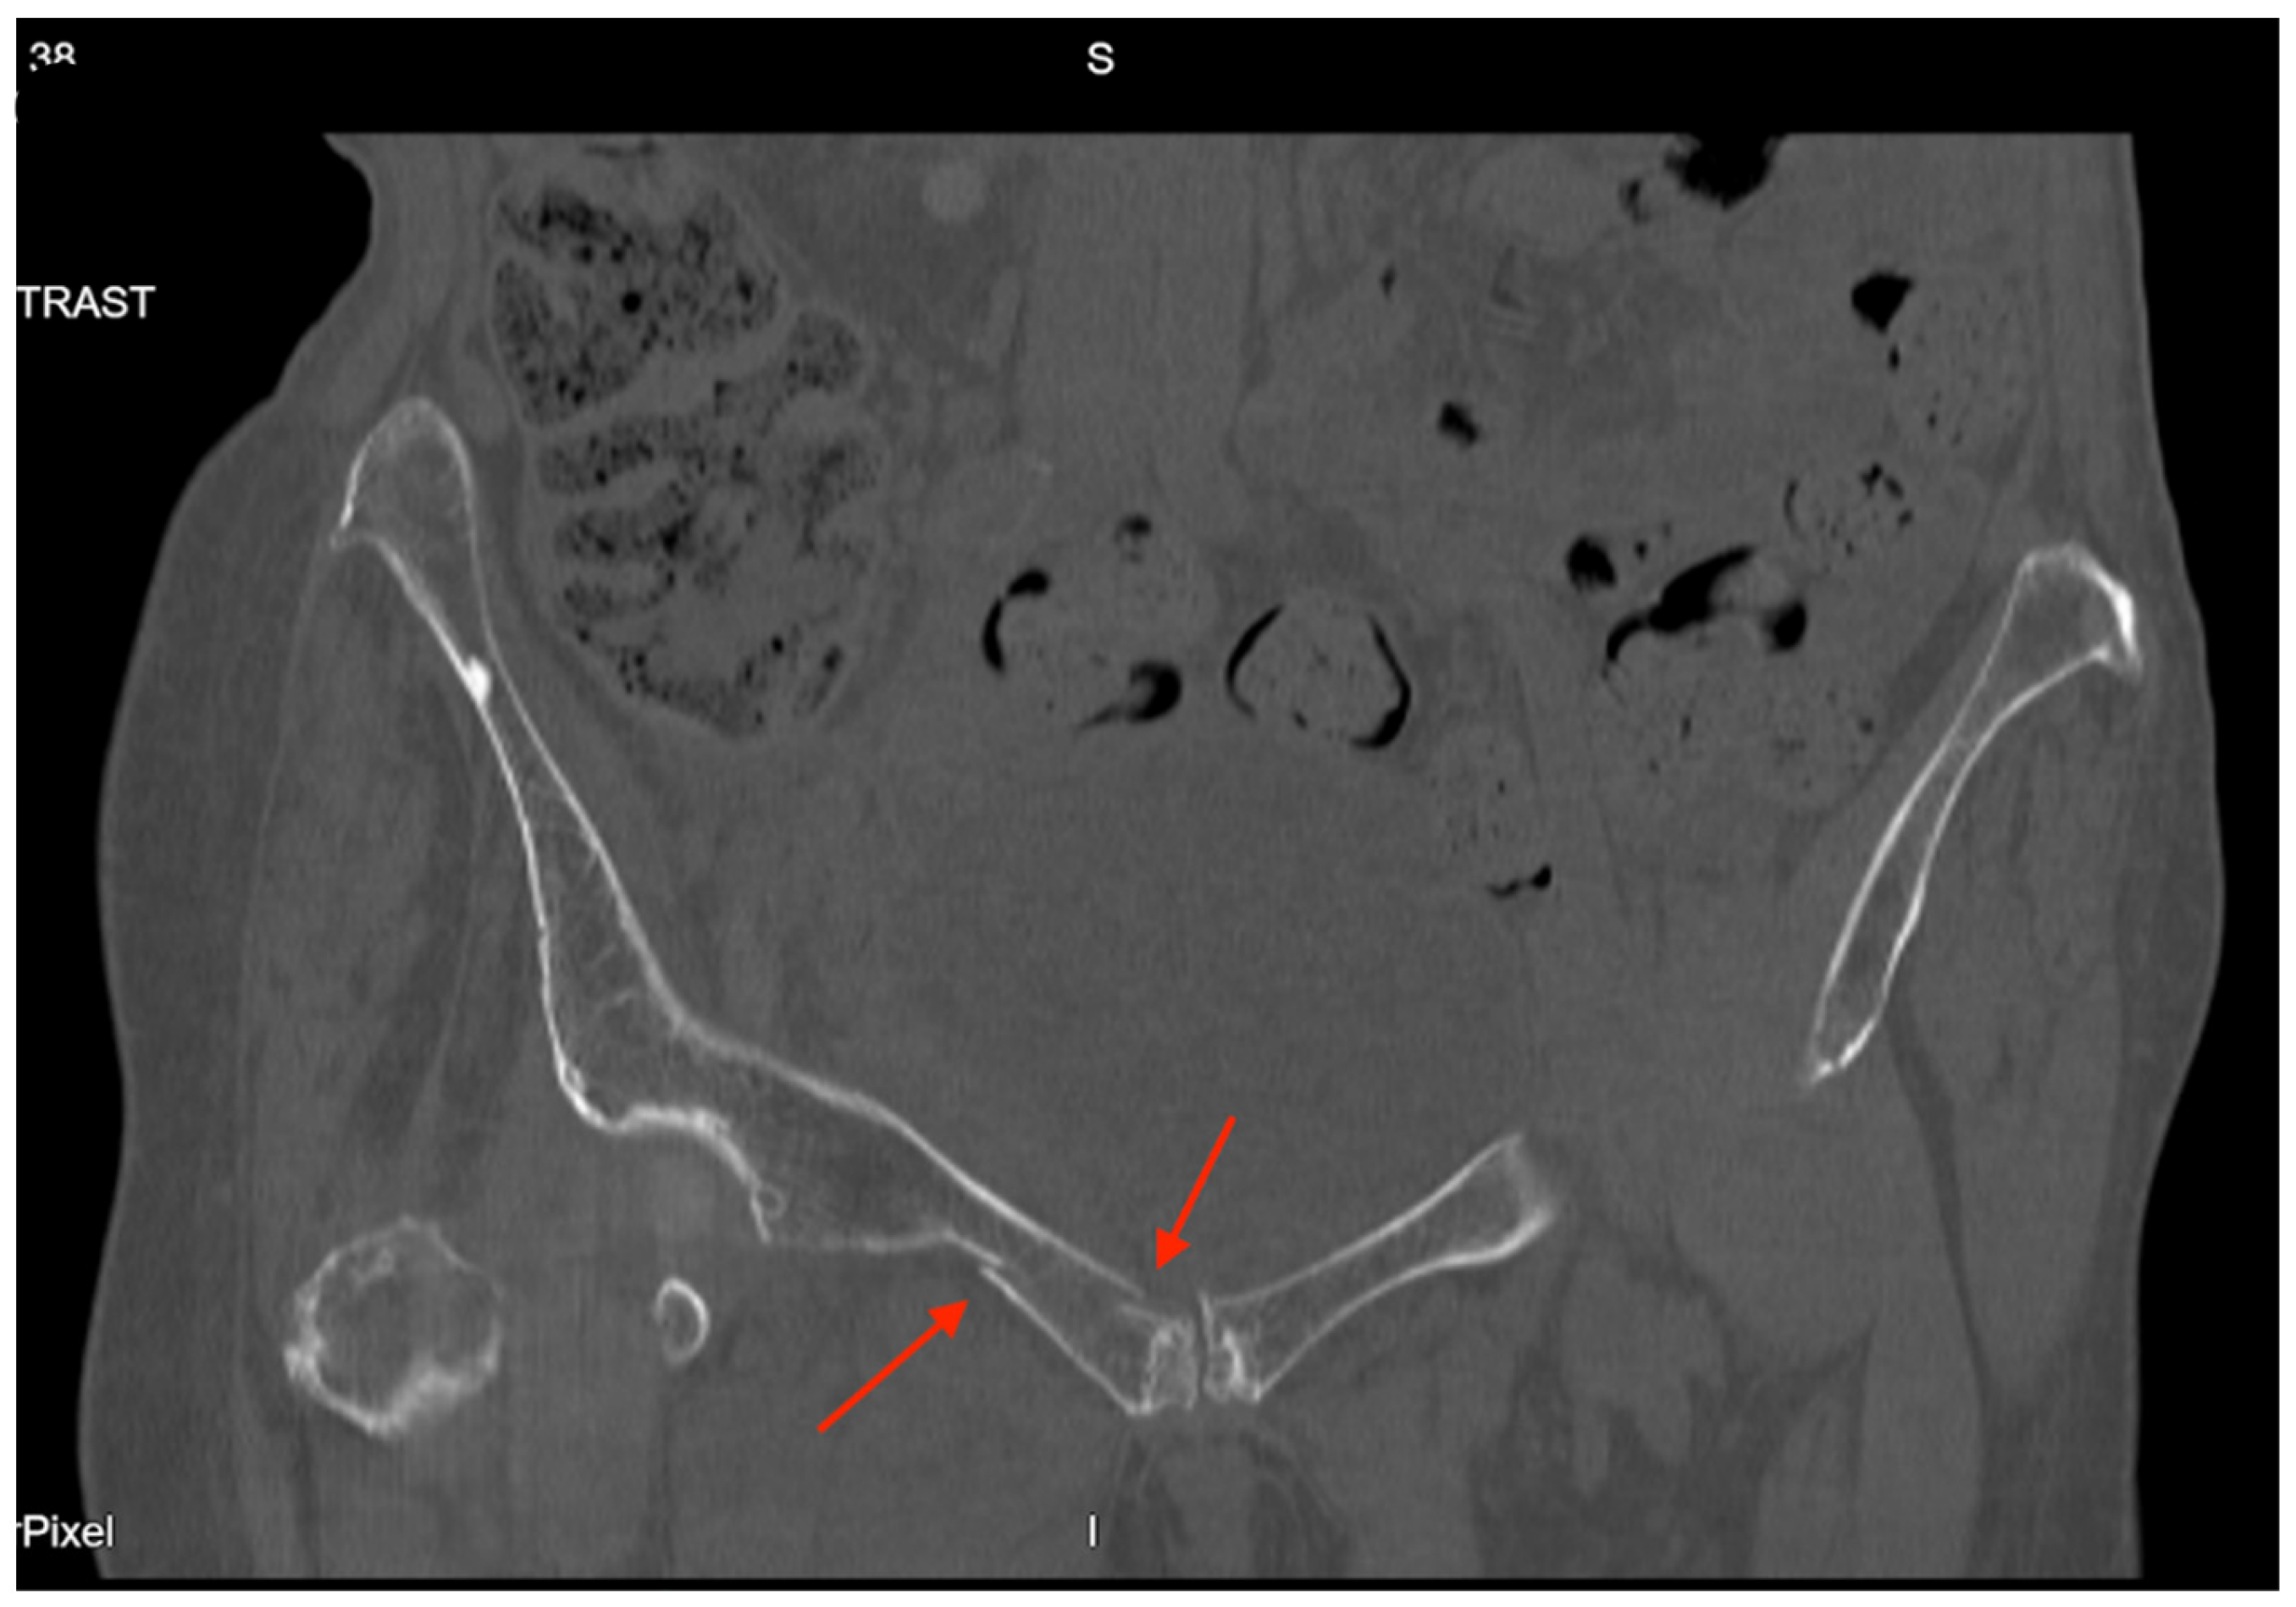

Pelvic imaging revealed acute fractures involving the right superior pubic ramus and left inferior pubic ramus, an acute comminuted avulsed fracture of the left sacral wing in the superior and midportion (Figure 1). Additional injuries included multiple facial fractures, left distal radius fracture, left femur fracture, and left tibial shaft fracture.

Figure 1. CT abdomen/pelvis images of the described fractures in case 1. Red arrows are used to indicate the location of pelvic fractures for easier identification.